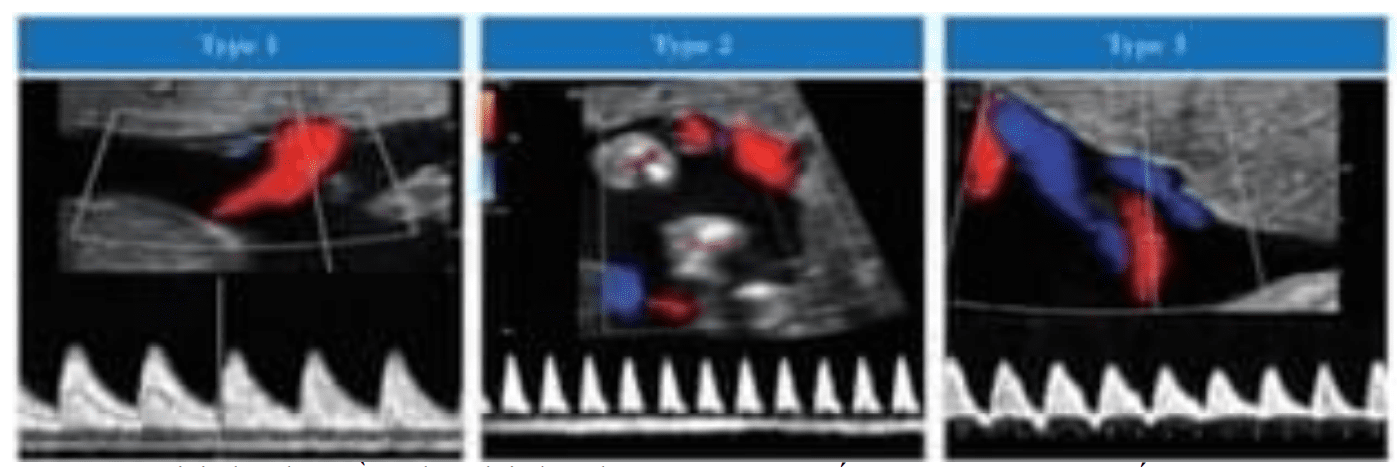

Hướng Dẫn Thực Hanh Isuog Vai Tro Của Sieu Am Trong Song Thai Thư Viện Y Học Lam Sang